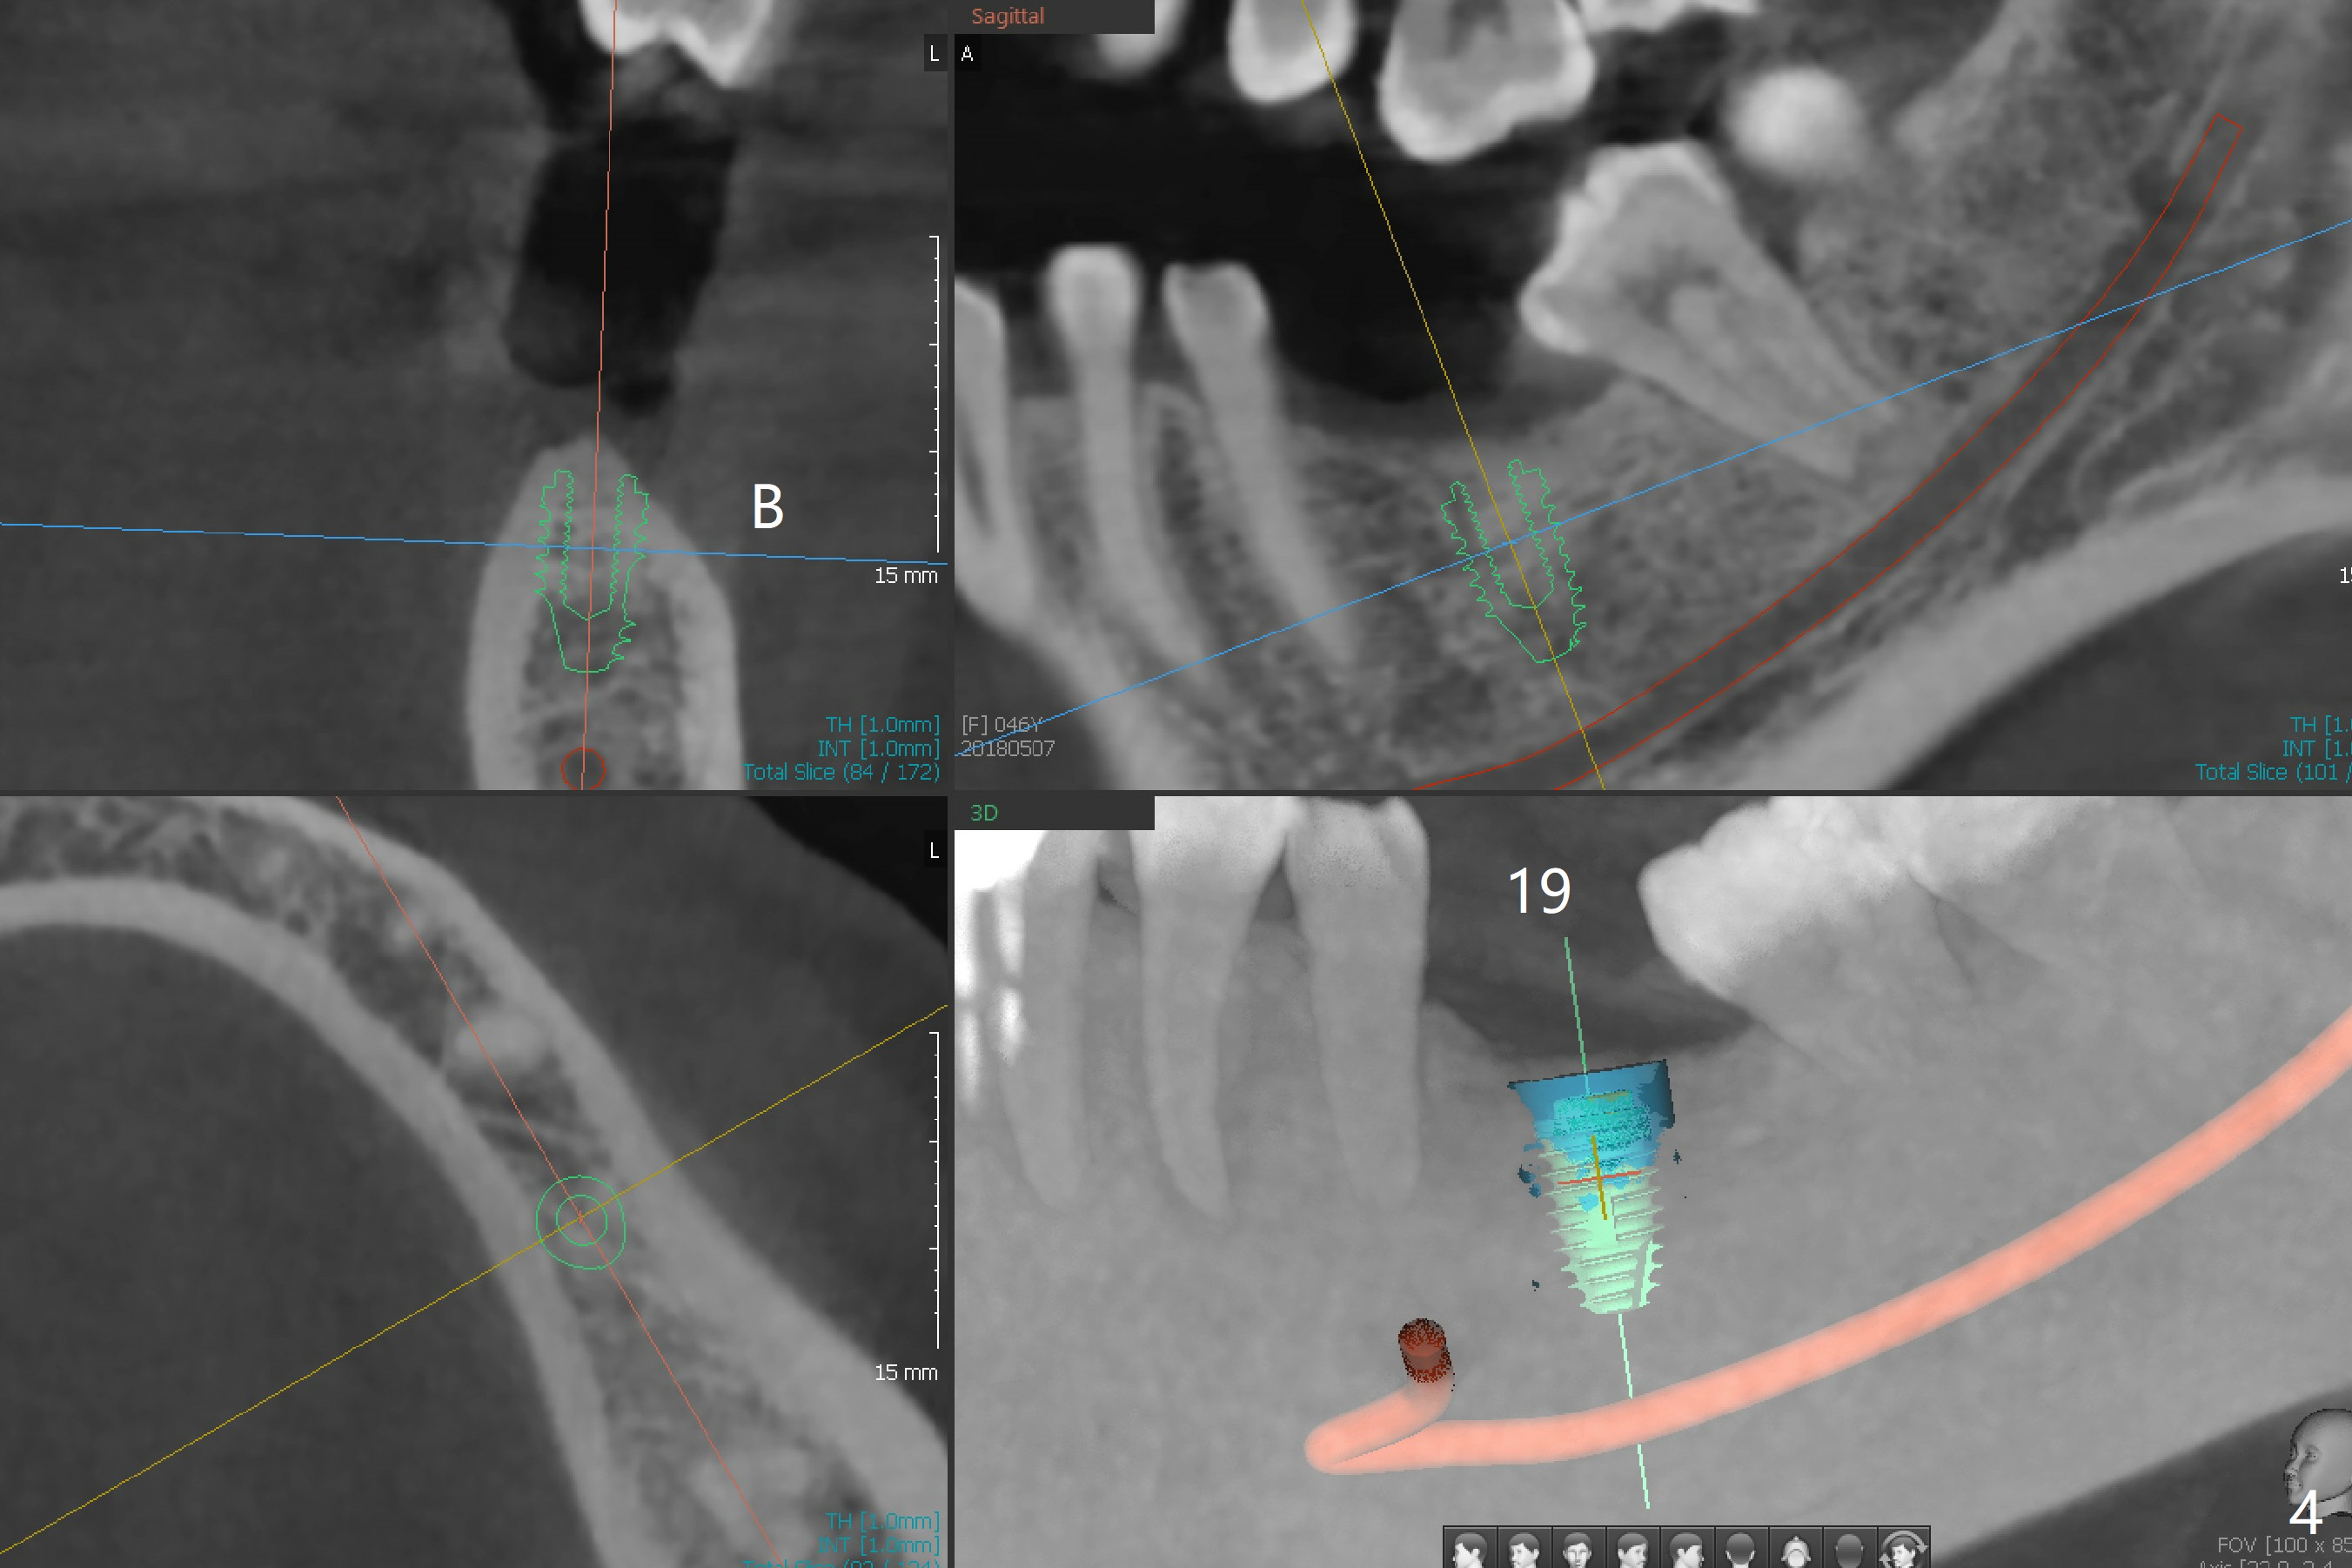

A 46-year-old woman has lost the tooth #19 since middle school with supraeruption of the tooth #14 and mesial tilt of the teeth #17 and 18 (Fig.1 arrows). After slightly distal placement of an implant at #19 with guided surgery (Fig.2), two minimplants will be placed for intrusion of the tooth #14. Upon implant osteointegration, a provisional will be fabricated with supraocclusion to facilitate the intrusion and upright the tooth #18 with extraction of the tooth #17. Fig.3 is a coronal section of CT of the roots of the tooth #14, showing 1.6x8 mm and 1.6x10 mm mini-implants to be placed mesiobuccal and distopalatal. A 5x8.5 mm implant will be placed at the site of #19 (Fig.4).